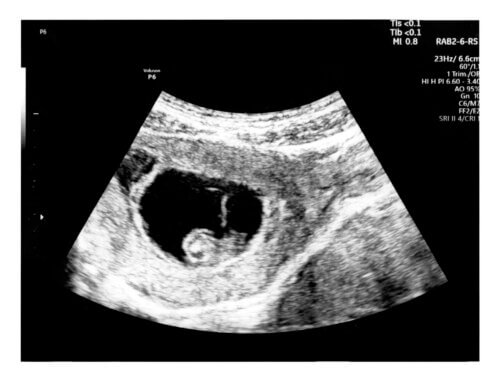

Dans cette échographie, il est possible d’observer la présence de l’embryon et d’évaluer l’état de santé des tissus maternels. De plus, avec cette échographie, on évalue les paramètres suivants :

- L’implantation correcte de l’embryon dans l’endomètre (c’est-à-dire la paroi interne de l’utérus). Le site de localisation et la taille de la vésicule gestationnelle, également connue sous le nom de sac gestationnel, sont observés.

- Le sac gestationnel. Il s’agit d’une petite sphère sombre, avec un bord clair, mesurant environ 8 millimètres à ce moment. Parmi ses fonctions les plus importantes, l’apport des nutriments nécessaires à l’embryon au cours des premières semaines se démarque. Dans cette structure se trouvent la cavité amniotique, le sac vitellin et le futur bébé.

- L’embryon. Bien qu’il soit encore trop petit pour être visualisé en détail, il est perçu comme un épaississement de la paroi du sac gestationnel, à proximité du sac vitellin. Dans le cas où il n’est pas possible d’objectiver à ce moment-là, le spécialiste prescrira une nouvelle échographie 2 semaines plus tard.

Au premier trimestre, l’échographie est réalisée par voie transvaginale. Car le bébé n’est pas assez grand pour être visualisé à travers l’abdomen.